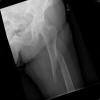

Fractura de cuello de fémur.